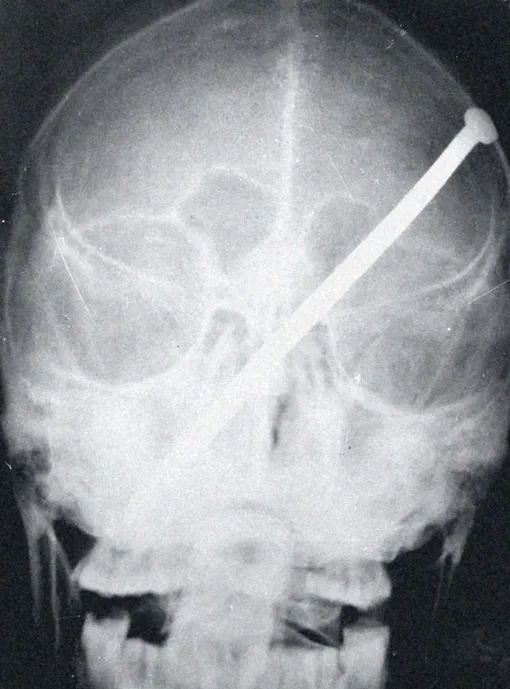

ЗИМБАБВЕ, 1976 ГОД

Гвоздь в черепе молодой женщины. Эту пытку применяют, чтобы доставить жертве дополнительные страдания и чтобы после смерти дух убитого не смог преследовать его мучителей. Жертва была еще жива, когда ее доставили в больницу и был сделан снимок, но позже она скончалась.